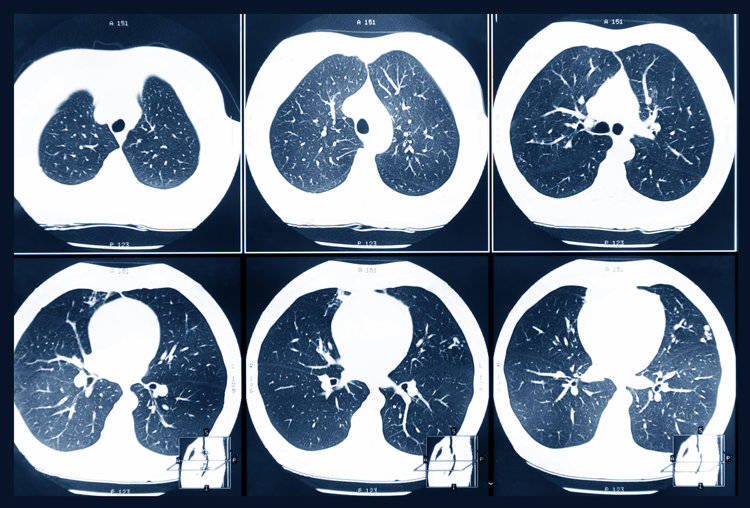

三、体检报告出现3个“字眼”,多半是肺癌前兆!很多人现在都有定期体检的习惯,如果在体检时发现报告上出现了这些字眼,一定要及时去专科就诊!1、持续性增大/直径≥8mm的肺结节肺结节是现代人身上的常见问题,但如果肺结节持续变大,随访3~6个月发现结节增大≥2mm,一定要高度警惕可能是恶性的。

还有就是查出直径≥8mm的肺结节,也可能是恶性的,概率为5~10%

2、磨玻璃结节/密度纯磨玻璃结节一般恶性的程度会低一些,如果是混合磨玻璃结节的话,则恶性程度会明显上升但也要结合结节的大小来进行判断,即便是纯磨玻璃结节,体积≥10mm,恶性程度也很高3、分叶状/毛刺征/胸膜凹陷征。

分叶状是指结节边缘不光滑,是由于肿瘤向各方向生长不均匀所致一旦发现结节有明显的分叶,恶性程度会明显增加;毛刺征则是指结节边缘呈细线状/毛刷状以放射状分布,这是由于肿瘤组织浸润周围组织生长所致,也可能是肿瘤周围的炎性反应导致的纤维化,一般是恶性肿瘤的征兆;。

胸膜凹陷征是结节和胸膜之间有明显的三角形、幕状影像,多在肺癌患者身上出现。